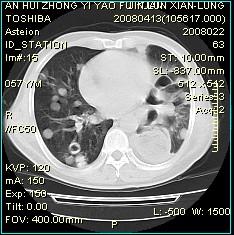

患者系食道癌术后2年,现复查胸部ct,片示;两肺实质内见多发大小不一的类圆形结节影,病灶沿肺纹理分布,以中下叶明显,边界清晰,较大病灶纵隔窗减影不明显,个别病灶内可见不规则偏心空洞影,双侧主支气管、叶段支气管通畅,纵隔内左侧后胸腔脊柱旁见胸腔胃影,腔-气间隙见一小淋巴结影,左侧胸膜增厚。

1.两肺多发结节影,结合临床病史考虑:食道癌术后两肺转移。

2.建议:随访

肺内转移瘤出现空洞,原发灶多为鳞癌。